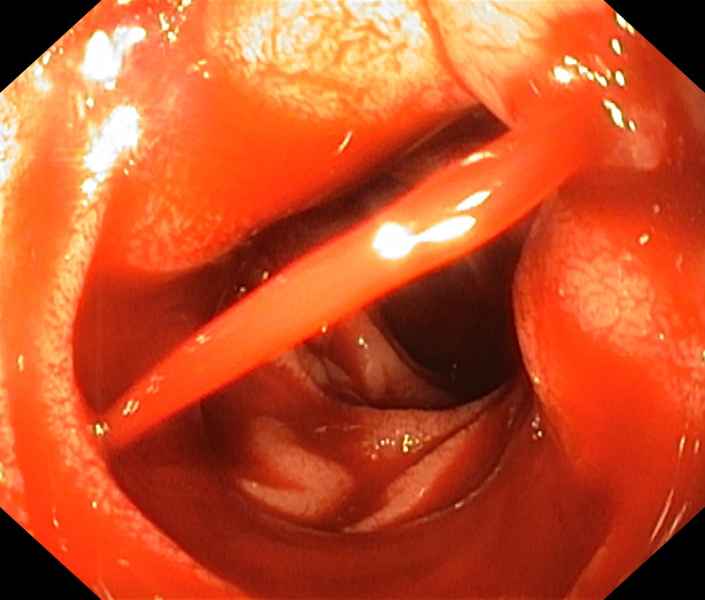

Rupture under the bridge, which way should I go?

Fotografia